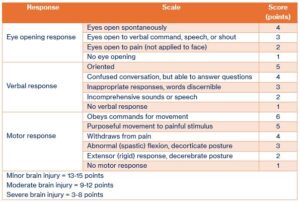

When someone experiences a brain injury, paramedics and doctors often check something called the Glasgow Coma Scale (GCS). It’s a simple way of seeing how awake, aware and responsive a person is right after the injury. The test looks at 3 things: how well the person opens their eyes, how they speak, and how they move.

The score helps them understand how serious the injury might be and what kind of care is needed.